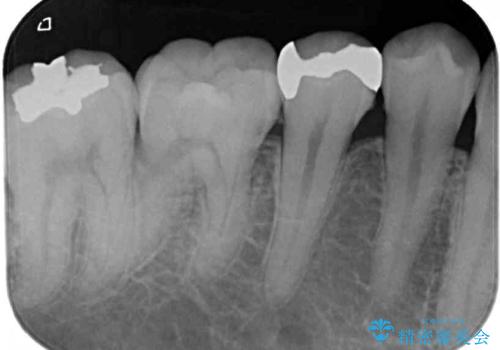

- 銀歯やむし歯でものが挟まるところが気になるとのことで来院された患者様です。

左上の奥歯は神経が失活しており、根管治療が必要な状態でした。

その他は銀歯のインレー(部分的な詰め物)が装着されており、それらはむし歯を除去した後にセラミックインレーにて修復治療を行い、左下と根管治療を行う左上の奥歯はオールセラミッククラウンにて補綴治療を行うこととしました。